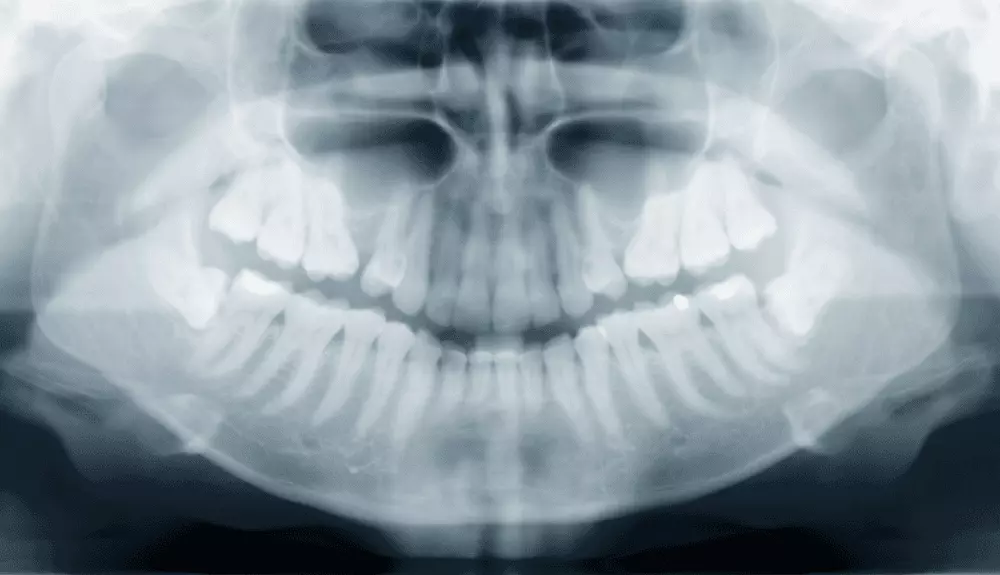

Stomatologia zachowawcza a próchnica zębów u dzieci

Jednym ze sposobów na zwalczanie próchnicy początkowej w stomatologii zachowawczej jest odpowiednia profilaktyka, polegająca m.in. na uszczelnianiu bruzd i szczelin. Skuteczność metody w zapobieganiu próchnicy zębów trzonowych wynosi ok. 90% po roku i do 50% po 5 latach. Jej zastosowanie wskazane jest m.in. w przypadku zębów z głębokimi bruzdami i szczelinami. Więcej na temat metod stosownych w stomatologii zachowawczej pisze dr n. med. Michał Sobczak.